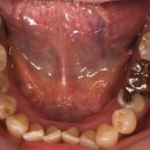

メタル修復の審美障害および二次カリエスに対しセラミックインレーへ置換した症例(50代女性)

治療前 治療後 相談内容 銀歯の見た目が気になること、詰め物の下の ...